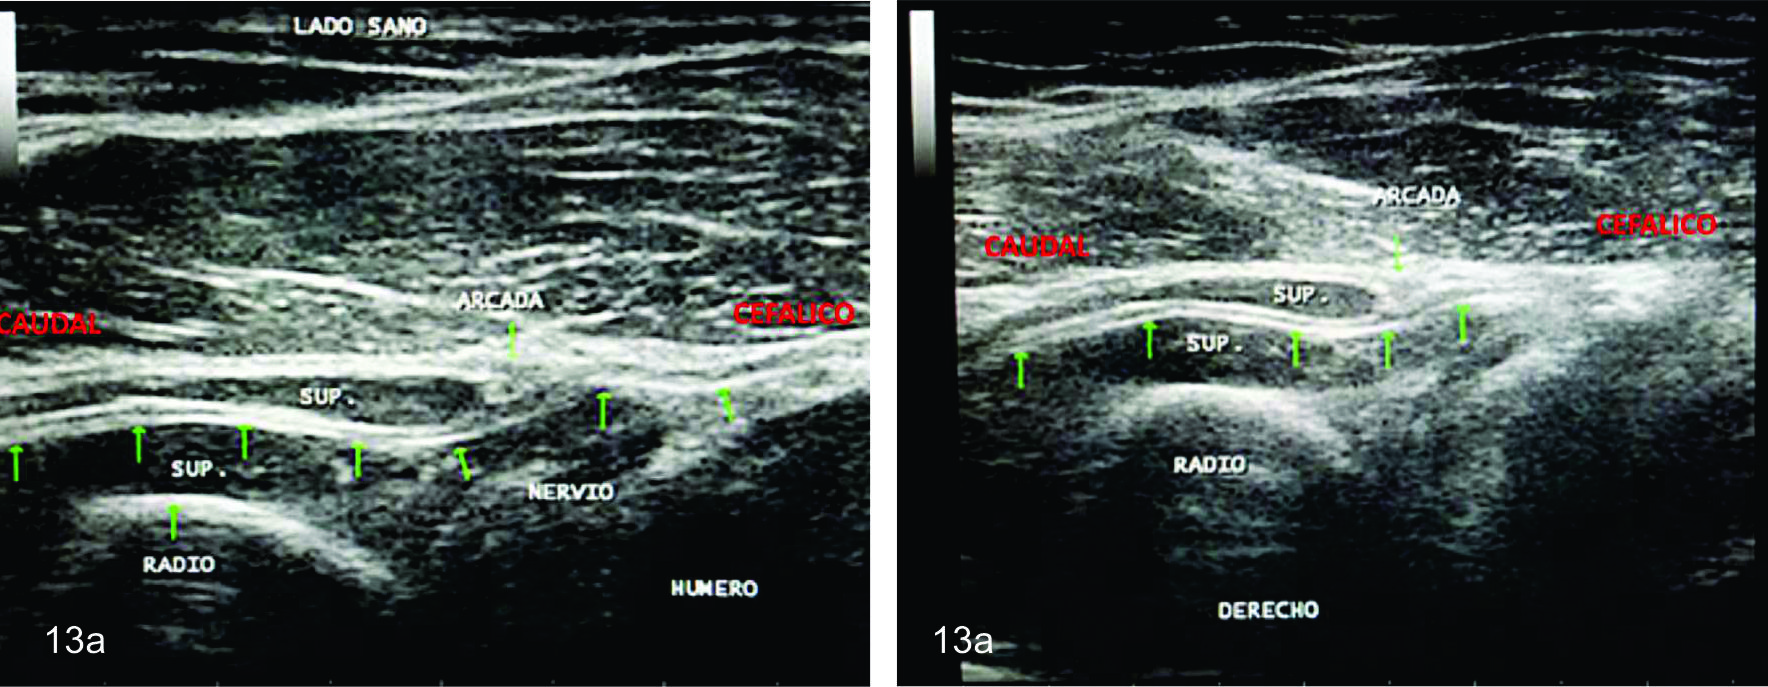

Figura 13 a

Síndrome interóseo posterior

Corte ultrasonográfico longitudinal del nervio interóseo normal- Se identifica en ambas imágenes el nervio (flechas verdes) como una estructura con forma de cuerda fina, con calibre uniforme cruzando el nivel de la articulación del codo e introduciendose entre ambos vientres del músculo supinador (SUP.)

Figura 13 b

Corte ultrasonografico longitudinal del nervio afectado (flechas verdes)- A- Se observa la transición entre el sector cefálico sano del nervio y la zona caudal neuropática. BSe identifica una compresión focal en el nivel de la acrada fibrosa cuando el nervio entra al espacio graso localizado entre ambas cabezas del supinador (Recuadro azul).